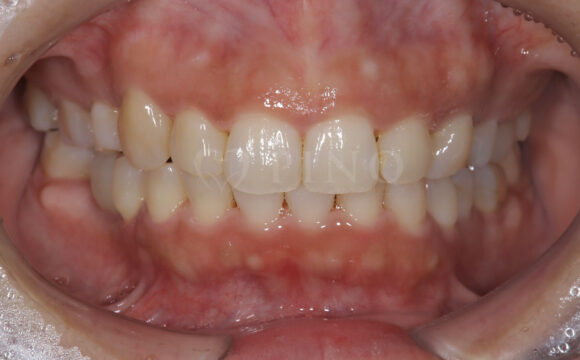

症例3:ワイヤー矯正後の後戻りが気になる(40代女性)

主訴 ワイヤー矯正後の後戻りが気になる 診断名 叢生 治療方法 マウスピース部分矯正 抜歯 なし オルソパルス なし 治療期間 9ヶ月 費用 436,000円 副作用・注意点 矯正後の後戻りを防ぐためリテーナーの使用が必要となる 備考 奥歯に噛み合わせ不良がない場合、部分矯正が適応となる -